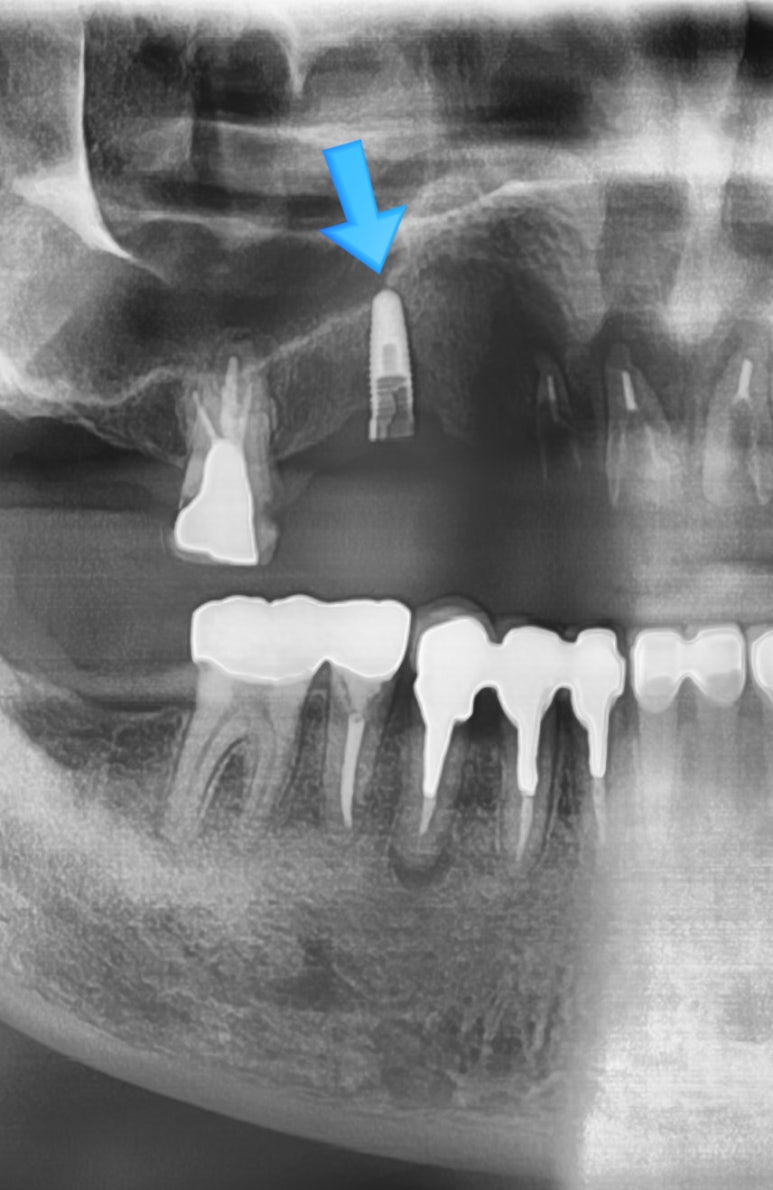

![[서울시청역/케이스]"다른 치과에서 한 임플란트가 흔들려서 빼야할 것 같아요" 관련 이미지 3](https://pub-9f2bb3498faf4d1d8714b41df24753e3.r2.dev/content/clinics/archive/rseeanjxfu/naver_blog/yonseiyegam/assets/by_hash/548cf67e60b75c9597d5704c4e423d73a8df8a9d8276430b562f576932287845.jpg)

![[서울시청역/케이스]"다른 치과에서 한 임플란트가 흔들려서 빼야할 것 같아요" 관련 이미지 4](https://pub-9f2bb3498faf4d1d8714b41df24753e3.r2.dev/content/clinics/archive/rseeanjxfu/naver_blog/yonseiyegam/assets/by_hash/1e8117be8f49c33957fc0d3e35492e69b7a919aad31daf92d18ddf8963516c88.jpg)

환자분이 처음에 오신 상태가 왼쪽 사진이고 많이 썩은 어금니와 임플란트픽스쳐를 제거한 것이 오른쪽 사진입니다.

환자분의 다른 치과에서 한 임플란트의 머리 부분은 없어진 상태이고 픽스쳐는 찢어져 있어서

픽스쳐 위에 지대주나 머리를 올릴 수 없어서 임플란트를 제거하는 수술을 하였습니다.